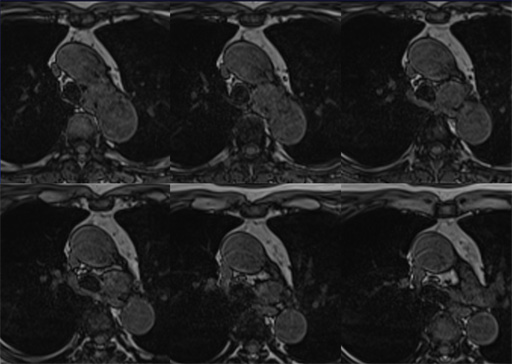

症例7 : 図9 MRI T2WI

症例7 : 図10 MRI fat sat T2WI

症例7 : 図11 MRI fat sat T1WI (dynamic study)